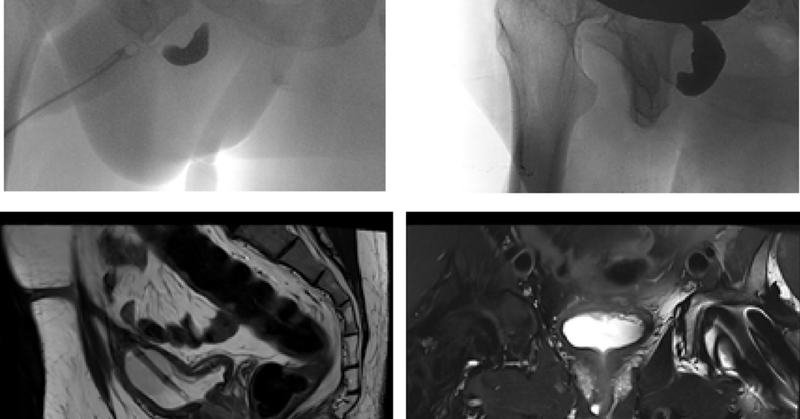

I am excited to share my research is now published! ๐Ÿ“š Posterior urethroplasty for pelvic fracture urethral injuries: risk factors for recurrence and complications https://t.co/h8NH7tjPvi @SN and #SNAuthor.

World Journal of Urology - Surgical reconstruction for posterior urethral injuries associated with pelvic fractures (PFUI) is complex. Perineal posterior urethroplasty via excision and primary...